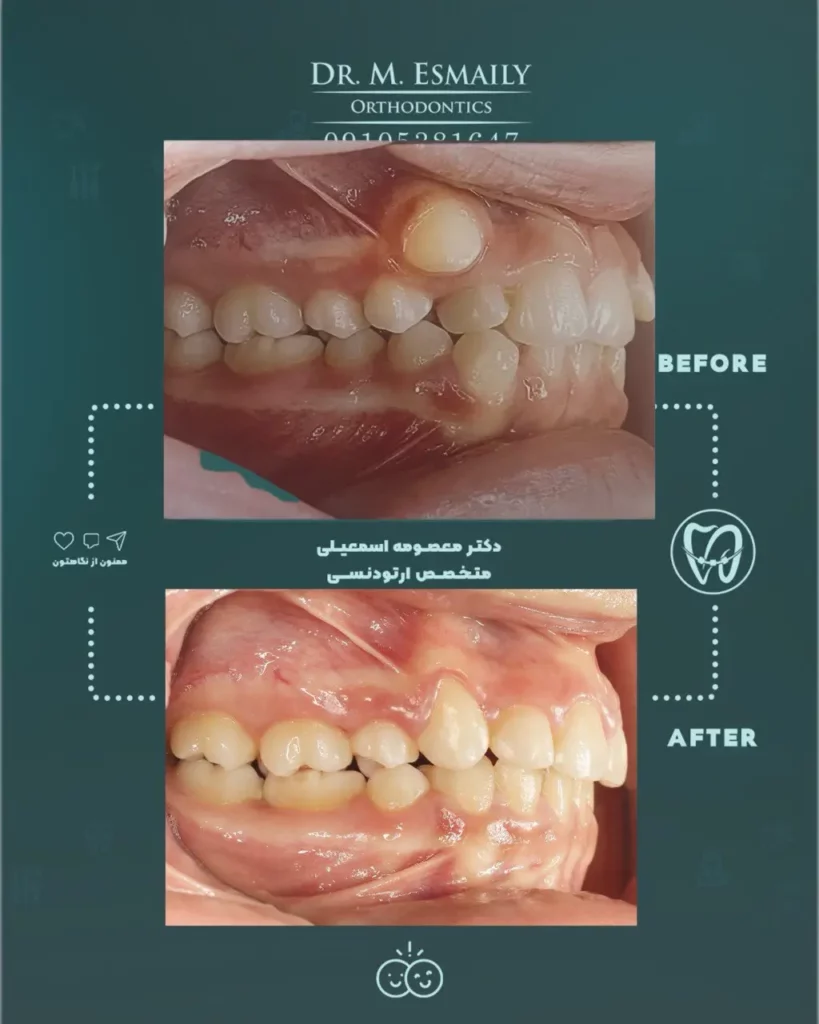

۵. دکتر معصومه اسمعیلی – دقت و ظرافت در درمان

آخرین پیشنهاد ما در لیست بهترین دکتر ارتودنسی غرب تهران، دکتر معصومه اسمعیلی است. ایشان با بهرهگیری از دانش روز و تجهیزات مدرن، سعی در ارائه درمانی با کمترین درد و بیشترین بازدهی دارند.

دکتر اسمعیلی دارای بورد تخصصی ناهنجاری های فک و صورت هستند. تمرکز ایشان بر ثبات نتایج درمان (عدم بازگشت دندان ها به حالت قبل) بعد از اتمام دوره ارتودنسی است که دغدغه بسیاری از بیماران می باشد. پیگیری دقیق وضعیت بیمار در طول ماه های درمان و در دسترس بودن برای پاسخگویی به سوالات و مشکلات احتمالی حین درمان از نقاط قوت این پزشک است.

🦷 نمونه درمان ارتودنسی دکتر معصومه اسمعیلی: